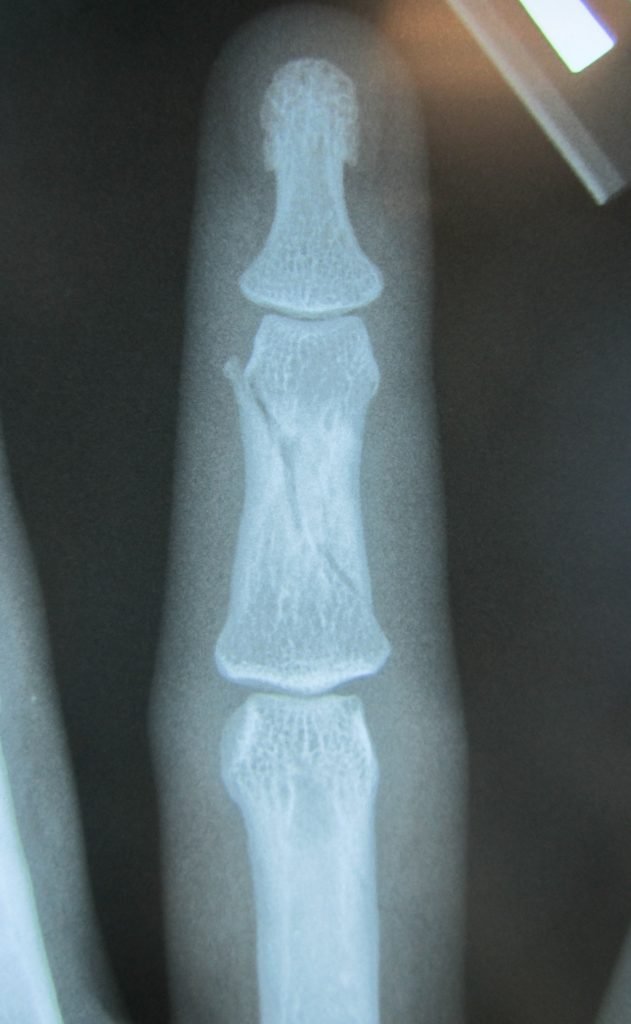

Fractures – everything you need to know

When we suffer a broken bone, we often get told to keep weight off it…. protect it…. 6 weeks until normality resumes…….. But what actually happens? So in this blog we are going to explain: 1) What happens when you fracture a bone? 2) How do fractures happen? 3) What are the clinical features of […]